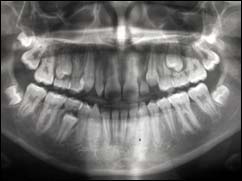

Panoramique

Cette radio permet d’appréhender l’ensemble de votre dentition et des structures adjacentes.